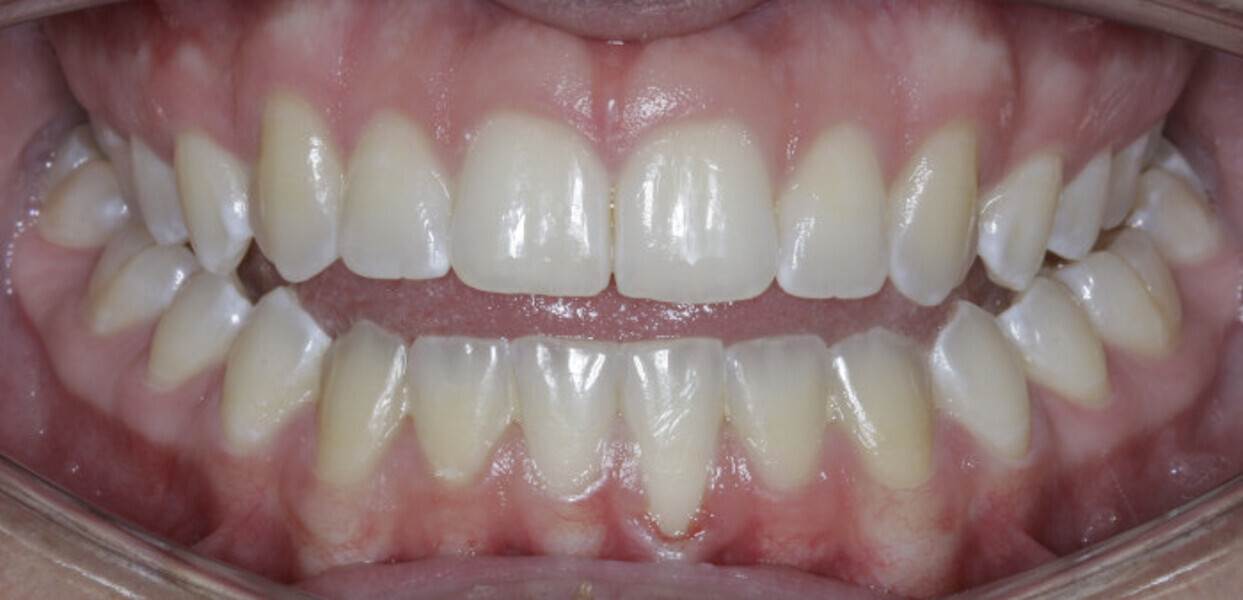

New Age orthodontics and orthopaedics with temporary anchorage devices